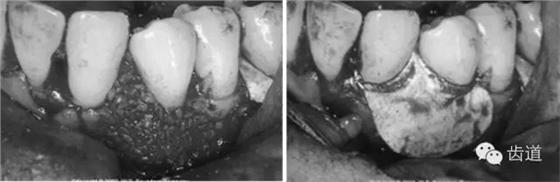

病損區(qū)常規(guī)行牙周翻瓣術(shù),去除感染的牙周袋內(nèi)壁上皮和肉芽組織,根面和骨面清創(chuàng)后,根據(jù)骨缺損和牙根外形選擇并修剪屏障膜,使之能完全覆蓋病損面并固定之,然后齦瓣復(fù)位嚴(yán)密縫合。

3、手術(shù)切口設(shè)計(jì)

需根據(jù)手術(shù)目的、預(yù)后、美觀效果等綜合平衡決定,可根據(jù)患者和病損區(qū)實(shí)際情況靈活選擇溝內(nèi)切口、內(nèi)斜切口、保留齦乳頭切口等,但要注意以盡量保留較多的角化牙齦組織為原則,也即要盡量多保留牙齦乳頭,以保證術(shù)后牙齦能覆蓋膜材料,避免外露導(dǎo)致感染、炎癥等。尤其在鄰面牙間隙處應(yīng)盡量選用齦乳頭保存術(shù)。一般應(yīng)做縱切口和在根方做松弛切口,以保證齦瓣能充分移動(dòng)和避免過大的張力。

創(chuàng)面和生物膜的覆蓋至關(guān)重要,如術(shù)后膜有暴露,極易污染,各種細(xì)菌將在膜上附著、增殖,進(jìn)而膜下空間會(huì)有急性炎性浸潤,導(dǎo)致再生過程停止。因此對術(shù)后牙齦瓣的松弛、覆蓋嚴(yán)密性和原位固定要求很高。

建議每一病例均結(jié)合采用二種縫合方式,一種是減張縫合,另一種則是對位縫合以關(guān)閉齦瓣。目的是充分保證齦瓣復(fù)位后能完全覆蓋住膜,在上端采取對位和懸吊縫合以防止膜和牙齦的根尖向移位,在鄰間隙處建議多采用水平交叉褥式縫合以削減過大的張力。